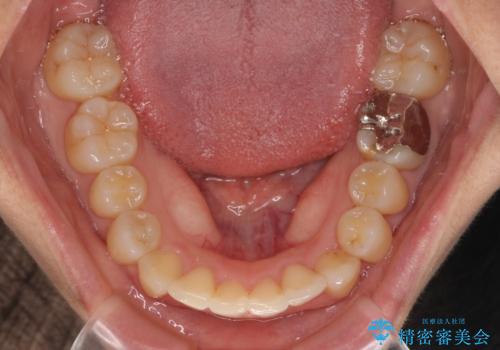

- 上下のクロスバイトと前歯のデコボコを気にして来院された患者様です。

インビザラインを用い、IPR(歯と歯の間を削る)と歯列全体を拡大させることで、歯並びを整えていくこととしました。